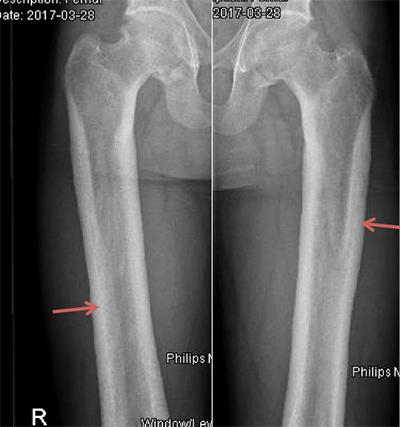

We described the case of a 23-year-old Nepalese man with seropositive rheumatoid arthritis and abnormal x-ray findings, found to be due to a very rare bone disease: Camurati Engelmann disease or progressive diaphyseal dysplasia (PDD). This is the first case reported in the Gulf area, although approximately 300 cases have been described worldwide. These patients usually present with limb pain and easy fatigability. Our patient first presented with bilateral, symmetrical inflammatory polyarthritis involving the knees, ankles and wrists but sparing the hands and feet. The diagnosis of PDD in our case was based on the classic radiological findings and a bone scan.

我们描述了一名23岁尼泊尔男性的病例,他患有血清阳性类风湿关节炎且X线检查结果异常,后来发现是由一种非常罕见的骨病引起的:卡穆拉蒂-恩格尔曼病或进行性骨干发育异常(PDD)。这是海湾地区报道的首例病例,尽管全球已描述了约300例。这些患者通常表现为肢体疼痛和易疲劳。我们的患者最初表现为累及双膝、双踝和双腕的双侧对称性炎性多关节炎,但手部和足部未受累。我们病例中PDD的诊断基于典型的放射学表现和骨扫描。